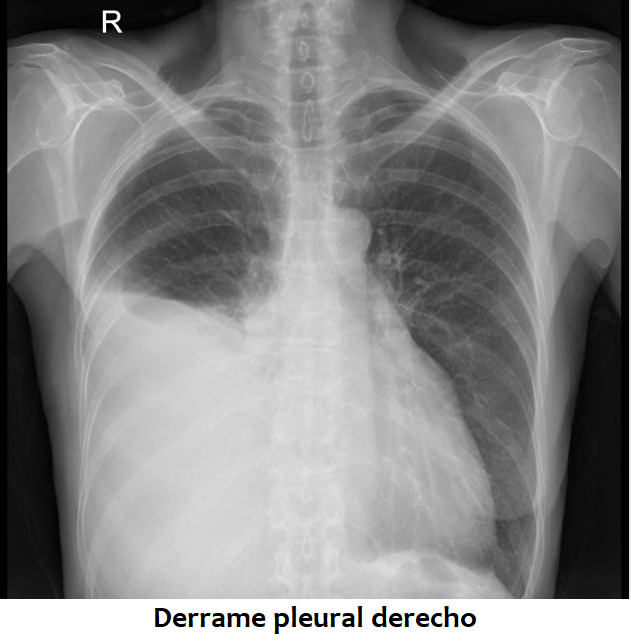

- Derrame pleural y empiema pleural